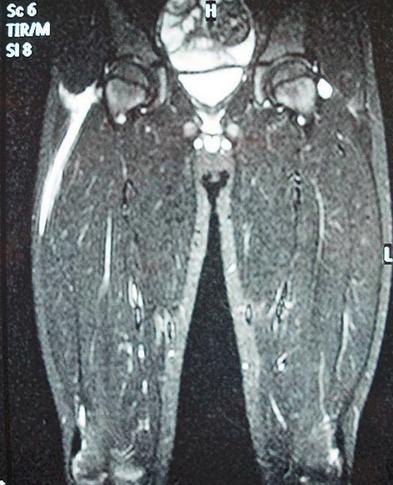

坏死性筋膜炎又称食肉菌感染,是一种广泛而迅速的皮下组织和筋膜坏死为特征的软组织感染,是一种非常罕见的感染性疾病。食肉菌专“吃”脂肪和筋膜,如果不及时清除,短时间内患者就会发展为中毒性休克、多器官功能衰竭甚至死亡。本病是多种细菌的混合感染,其中主要是化脓性链球菌和金黄葡萄球菌等需氧菌。本病感染只损害皮下组织和筋膜,不累及感染部位的肌肉组织是其重要特征。

(1)片状红肿、疼痛:早期皮肤红肿,呈紫红色片状,边界不清,疼痛。此时皮下组织已经坏死,因淋巴通路已被迅速破坏,故少有淋巴管炎和淋巴结炎。感染24h内可波及整个肢体。个别病例可起病缓慢、早期处于潜伏状态。受累皮肤发红或发白、水肿,触痛明显,病灶边界不清,呈弥漫性蜂窝织炎状。

(3)血性水疱:由于营养血管被破坏和血管栓塞,皮肤的颜色逐渐发紫、发黑,出现含血性液体的水疱或大疱。

(4)奇臭的血性渗液:皮下脂肪和筋膜水肿、渗液发黏、混浊、发黑,最终液化坏死。渗出液为血性浆液性液体,有奇臭。坏死广泛扩散,呈潜行状,有时产生皮下气体,检查可发现捻发音。